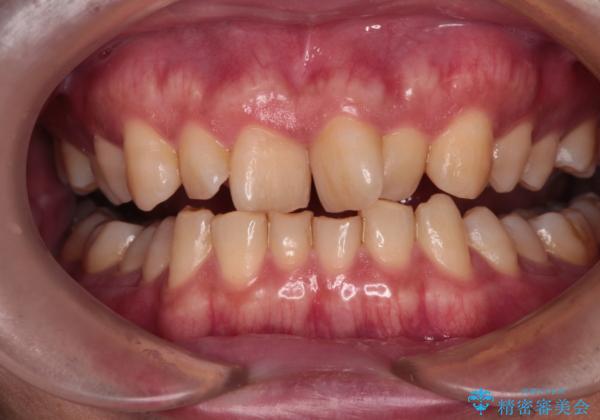

- 前歯のデコボコと深い咬み合わせを気にして来院された患者様です。

骨格的に上顎骨がやや前方にあり、それが原因で下顎前歯が隠れるほどのディープバイトになっている状態でした。